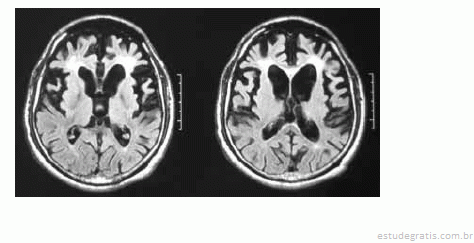

Uma mulher de 55 anos de idade, sem comorbidades, há três anos começou a apresentar distúrbio do comportamento, comprometimento do senso moral, da autocrítica, do poder de abstração e da memória. No exame, ela pouco colaborava com o examinador, possuía uma rigidez axial e apendicular, além de sutil tremor em repouso. O exame de imagem (RNM) a seguir foi realizado para auxiliar o diagnóstico.

Com base nesse quadro clínico, julgue os itens subsequentes.

Caso a paciente apresente paralisia do olhar horizontal associado aos sintomas descritos, deve-se tratar de paralisia supranuclear progressiva.Comentários